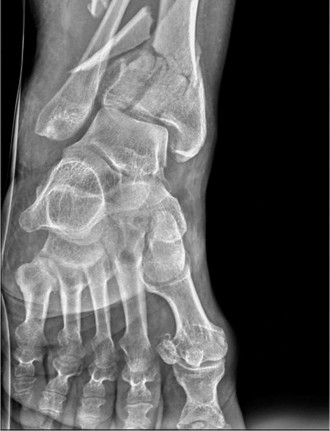

Standard trauma radiographs, including anteroposterior, lateral, and mortise views of the right ankle and full-length tibia and fibula, were obtained.

The radiographs demonstrated a highly comminuted, completely displaced intra-articular fracture of the distal tibia, classically defined as a pilon fracture. The articular surface of the tibial plafond was severely disrupted, with multiple articular fragments impacted proximally into the metaphyseal void. Significant metaphyseal comminution was present, resulting in a profound loss of tibial length and varus malalignment of the distal segment.

A concomitant, highly comminuted fracture of the distal fibula was identified at the level of the syndesmosis, contributing significantly to the loss of lateral column support and the total collapse of the ankle mortise integrity. The talus appeared displaced proximally and anteriorly, following the path of least resistance created by the axial loading mechanism and the destruction of the anterior tibial rim.

While the plain radiographs provided a macroscopic overview of the catastrophic osseous failure, the true complexity of the articular comminution, the degree of central die-punch impaction, and the exact orientation of the major fracture lines could not be fully appreciated.